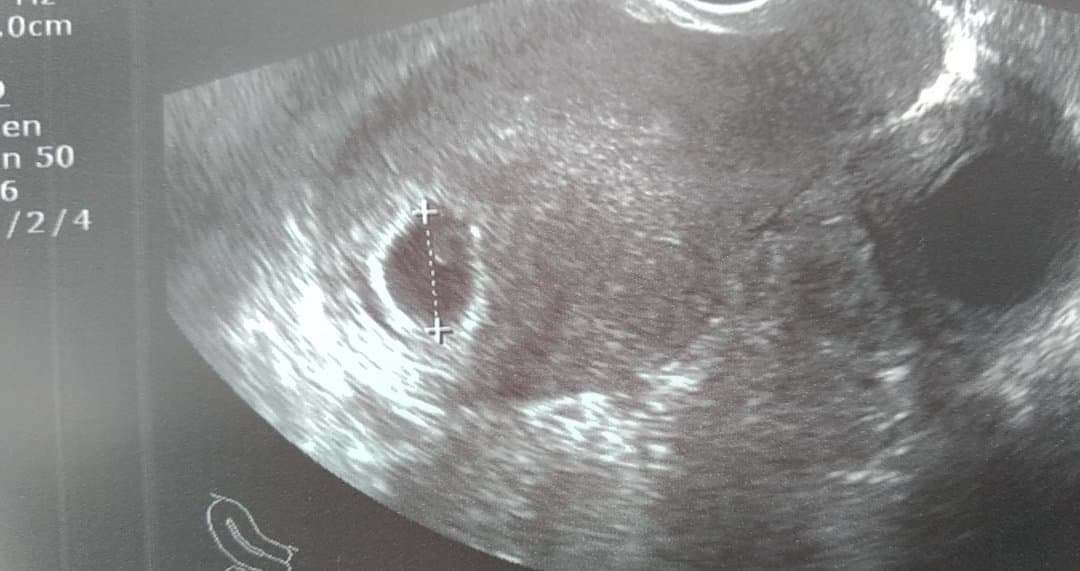

superByłam dzisiaj na pierwszej wizycieciąża 4 i pół tygodnia, kolejna wizyta za 2 tygodnie i mam nadzieję że będzie już słychać serduszko

![]()

który to tydzień. Było już serduszko?Niestety z krwiakiem obok, ale liczę że się wchłonie [emoji106][emoji4]Zobacz załącznik 1129190

Jeszcze nic nie mówił o serduszku, za tydzień mam znów przyjść. 6tc.który to tydzień. Było już serduszko?